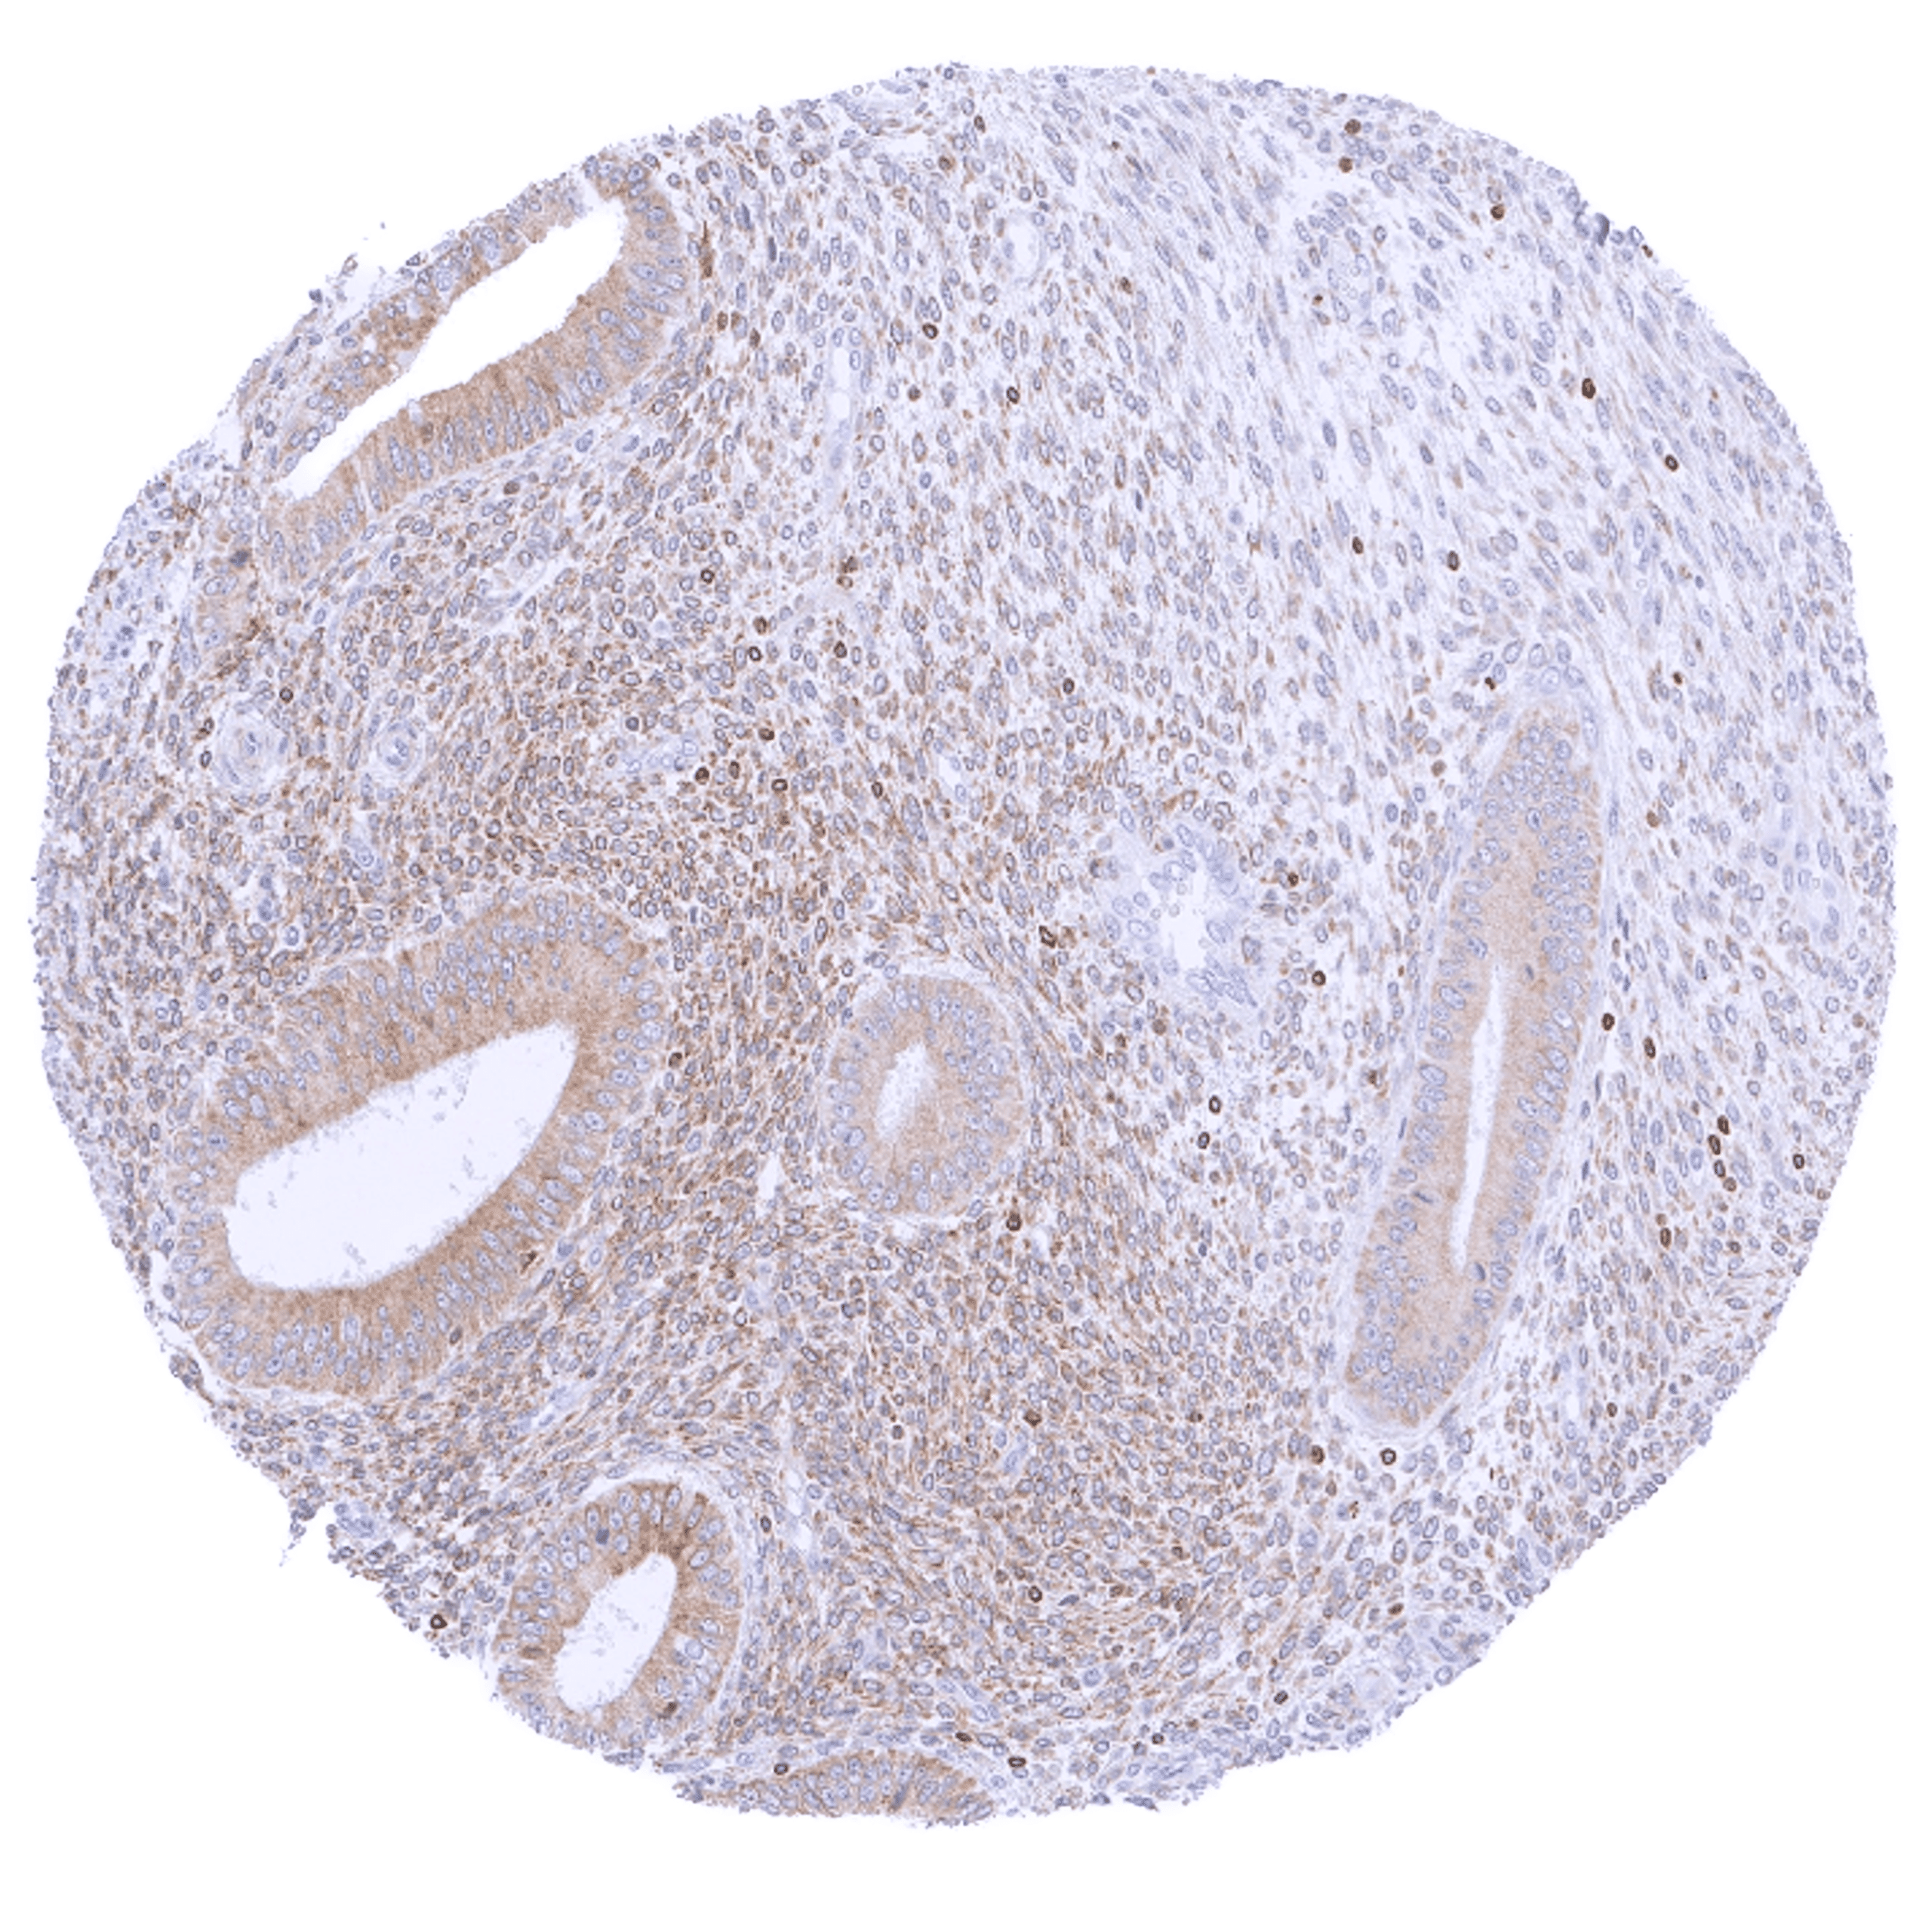

Positive control = Tonsil: A strong cytoplasmic bcl-2 staining should be seen in most interfollicular lymphocytes while most germinal centre cells are bcl-2 negative.

Negative control = Tonsil: The vast majority of lymphocytic cells from germinal centres must be bcl-2 negative while interfollicular lymphocytes are mostly positive.

| Tonsil | Strong bcl-2 positivity of a large fraction of lymphocytic cells in the interfollicular area and around germinal centres while almost all cells in germinal centres are bcl-2 negative. Squamous epithelium is bcl-2 negative although the basal cell layer may show weak positivity. | |